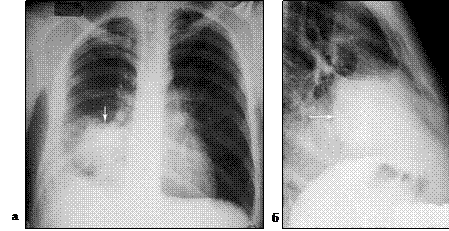

По-прежнему базовым методом подтверждения клинического диагноза бактериальной деструкции легкого остается полипозиционная рентгеноскопия и рентгенография грудной клетки, позволяющая подтвердить диагноз и определить локализацию процесса. При остром абсцессе легкого до сообщения его с бронхиальным деревом определяется правильная округлая гомогенно затемненная полость с перифокальной инфильтрацией (рис. 1). После опорожнения гнойника в дыхательные пути – полость с уровнем жидкости (рис. 2).

Рис. 1. Блокированный абсцесс средней доли правого легкого (отмечен стрелкой). Рентгенограмма грудной клетки в прямой (а) и правой (б) боковой проекции.